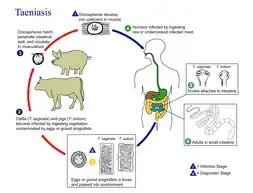

O ciclo de vida dos eucéstodes é menos complexo do que o dos Digenea, mas varia em função da espécie ou do género a que esta pertence. Por exemplo:

- Várias espécies de Taenia infestam os intestinos de humanos, gatos e cães. Os juvenis usam herbívoros, entre os quais porcos, bovinos e coelhos, como hospedeiros intermédos. Os proglotes excretados libertam ovos que se colam às folhas das plantas e que eclodem após serem ingeridos por um herbívoro. A larva move-se através dos tecidos do herbívoro até atingir uma massa muscular, na qual se metamorfoseia num verme oval, com cerca de 10 mm de comprimento, com um escólex que é mantido recolhido. Quando o hospedeiro definitivo comer a carne crua (ou mal cozida) do hospedeiro intermédio, o escólex do parasita abre-se e fixa-se à parede do intestinot, seguindo-se o desenvolvimento do adulto e o fecho do ciclo de vida.[8]

Interação com os humanos

Os Cestoda (ténia e similares) e os Digenea (tremátodes e similares) são a causa importantes patologias em humanos e em animais domésticos. Os Monogenea, parasitas de peixes, podem causar importantes perdas em instalações de aquacultura.[39] Um doença com esta origem, a bilharziose, também conhecida por esquistossomose ou doença-do-caramujo, é a segunda patologia mais expandida e devastadora da saúde das populações humanas das regiões tropicais, apenas ultrapassada pela malária.

O Carter Center estimou que 200 milhões de pessoas, em 74 países, estão infestadas com o parasita causador da bilharziose, sendo que metade destas pessoas vivem na África sub-sariana. Apesar da condição ter uma baixa taxa de mortalidade, assume frequentemente um carácter de doença crónica que progressivamente danifica os órgãos internos do paciente. Pode influenciar negativamente o crescimento e o desenvolvimento cognitivo de crianças e aumentar significativamente o risco de cancro da bexiga em adultos. A doença é causada por diversas espécies do género Schistosoma, os quais podem perfurar a pele humana penetrando por essa via no corpo. As pessoas em maior risco são as que utilizam corpos de água infestados para recreio ou para lavagem de roupas.[35]

No ano 2000, estimava-se que 45 milhões de de pessoas estavam infestadas coma ténia Taenia saginata, originária de carne bovina infestada, e 3 milhões com a espécie Taenia solium, de origem suína.[39] A infecção do sistema digestivo por ténias adultas causa sintomas abdominais considerados desagradáveis e debilitantes, mas em geral não causam incapacidade ou ameaçam a vida.[40][41] A neurocisticercose, resultante da penetração de larvas de T. solium no sistema nervoso central, é a principal causa de epilepsia adquirida a nível global.[42] Em 2000, cerca de 39 milhões de pessoas estavam infectadas com tremátodes que na natureza parasitam peixes e crustáceos, mas que podem ser transmitidos aos humanos pela ingestão da peixe ou de crustáceos crus ou mal passados. A infecção de humanos pela espécie Diphyllobothrium latum, um parasita de peixes, causa difilobotríase da qual ocasionalmente resulta deficiência de vitamina B12 e, em casos severos, anemia megaloblástica.[39]